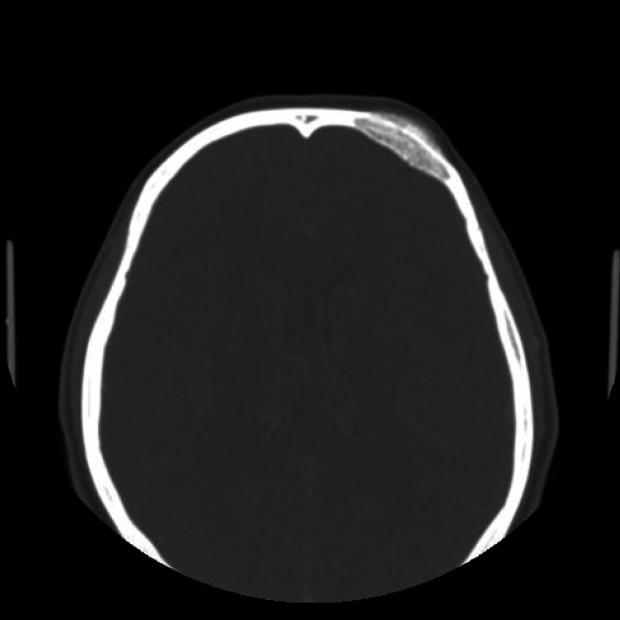

Primary intraosseous hemangioma in the frontal bone.

Primary intraosseous hemangioma in the frontal bone.额骨原发性骨内血管瘤